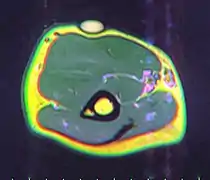

Ultrasonography of a liposarcoma for comparison: In this case a heterogeneous mass consisting of an upper hyperechoic portion, corresponding to lipomatous matrix, and areas of hypoechogenicity corresponding to nonlipomatous components.[22]